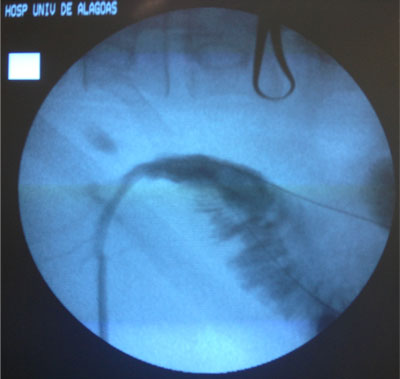

- Drenagem da Via Biliar e Dilatação da Estenose;

Dilatação com balão

- Balões maiores -> utilizados para a estenose do ducto biliar comum;

- Anastomoses biliares entéricas -> dilatação com um balão maior (10 a 20 mm de diâmetro);

O tipo da estenose é importante na definição da resposta do dilatação.

Estenoses de anastomose X Estenoses não anastomótica

Estenose recorrente após dilatação de estenose biliar benigna pode ocorrer em 29-58% dos casos;

Para evitar esta complicação -> pode ser necessário “stent”. Uso do stent após a dilatação é controverso -> sucesso a longo prazo x pode estimular reação inflamatória, fibrose e formação de cálculos;

Nos últimos 30 anos, o tratamento percutâneo da estenose biliar benigna, com dilatação com balão e implante de stent, tem sido amplamente aceito como uma opção terapêutica válida com baixa taxa de complicações.